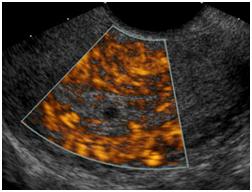

Your doctor has ordered an ultrasound of your pelvis. Ultrasound is a safe and painless procedure that uses sound waves to assess the structure of your internal body organs. The scan can help diagnose such medical conditions as pelvic masses in the uterus and ovaries.

- Sound waves will bounce off certain organs and tissue in your body. This creates "echoes." The echoes are reflected back to the transducer, which converts them to electronic signals. A computer then processes the signals into pictures for radiologist evaluation.

- After the uterus and ovaries are scanned through the full bladder from outside, you will be allowed to use the restroom to completely empty your bladder. You will then change into a gown and the technologist will complete the second part of the exam. A long transducer will be guided through the cervix to get visually closer and more detailed imaging of the uterus and ovaries.